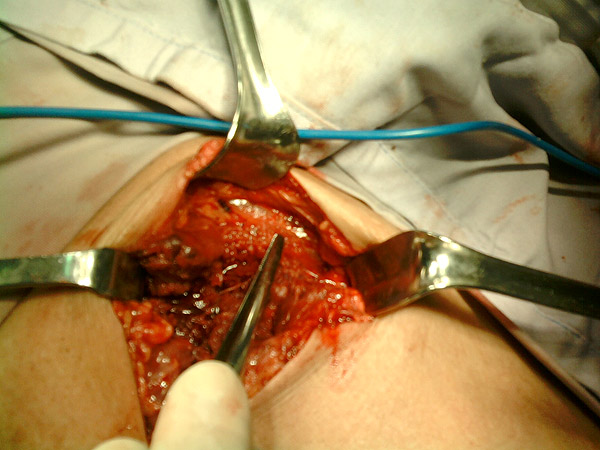

Desbridación de la herida

Explorando las trayectorias